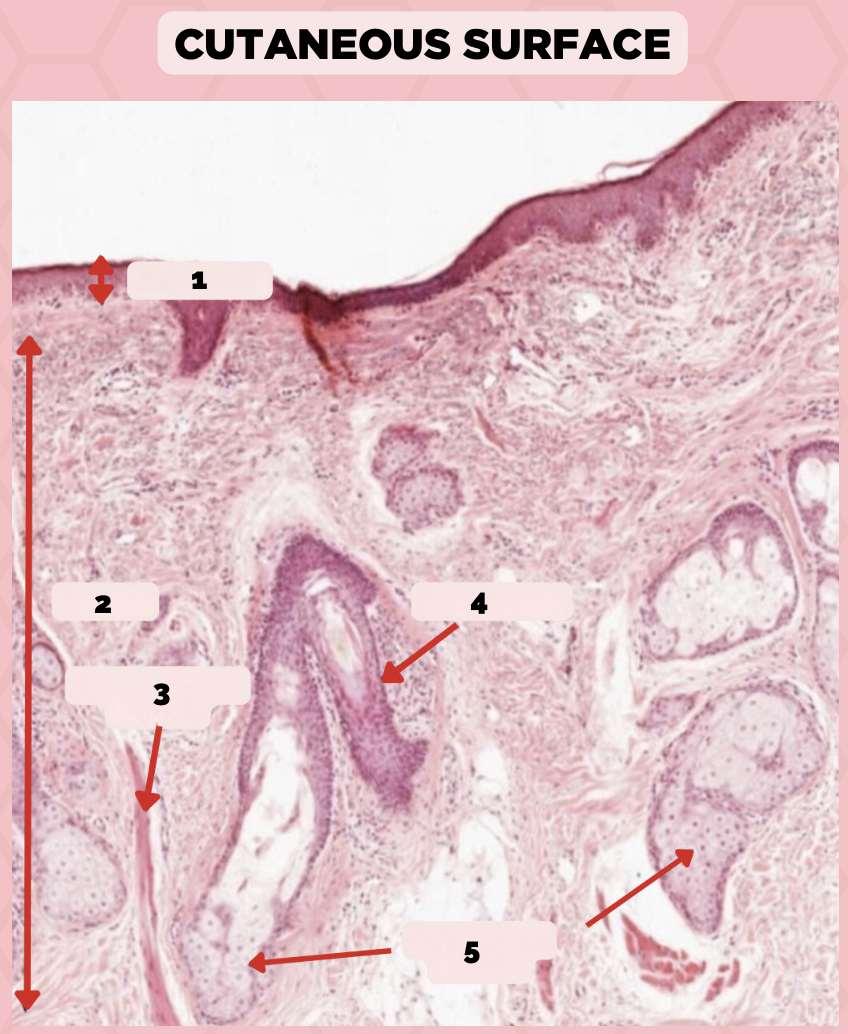

Lip

What specimen is being showed in the picture?

Epidermis

Identify the structure labeled as 1.

Dermis

Identify the structure labeled as 2.

Arrector Pilli Muscle

Identify the structure labeled as 3.

Hair Follicle

Identify the structure labeled as 4.

Sebaceous Glands

Identify the structure labeled as 5.